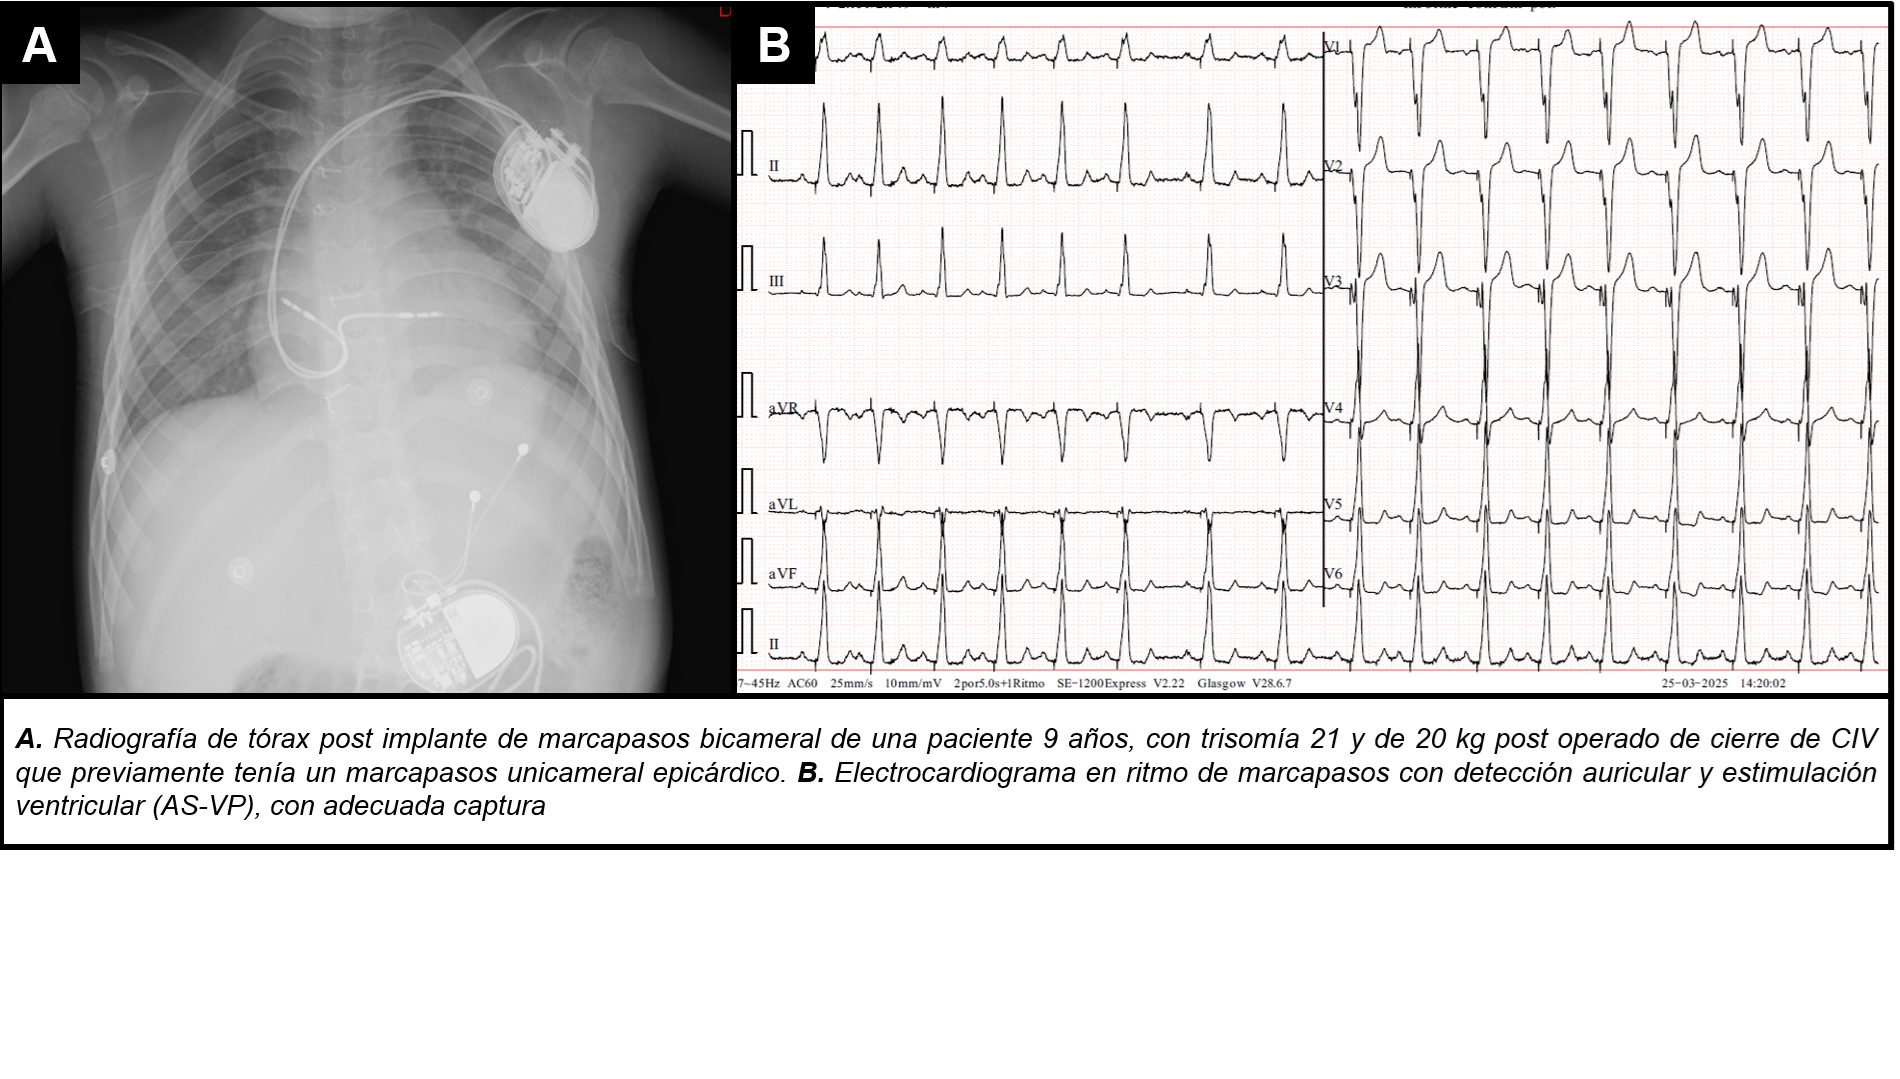

Introducción: El cierre quirúrgico de un CIV peri membranoso, puede traer como...